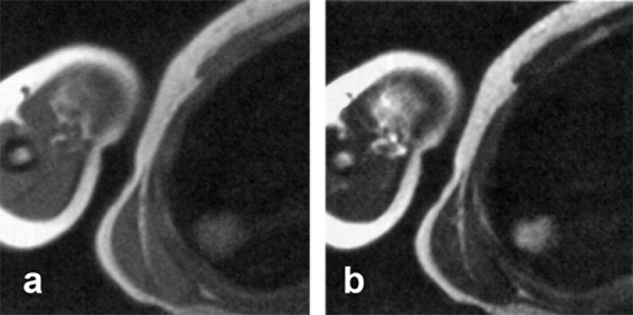

Figure 17-03:

(a) Transverse intermediately, and (b) T2-weighted images depict an ill-defined high signal in­­ten­­si­­ty le­sion in the right lung. Follow-up studies on another day and the use of CT did not show such a lesion. The cause of the artifact remained unclear.